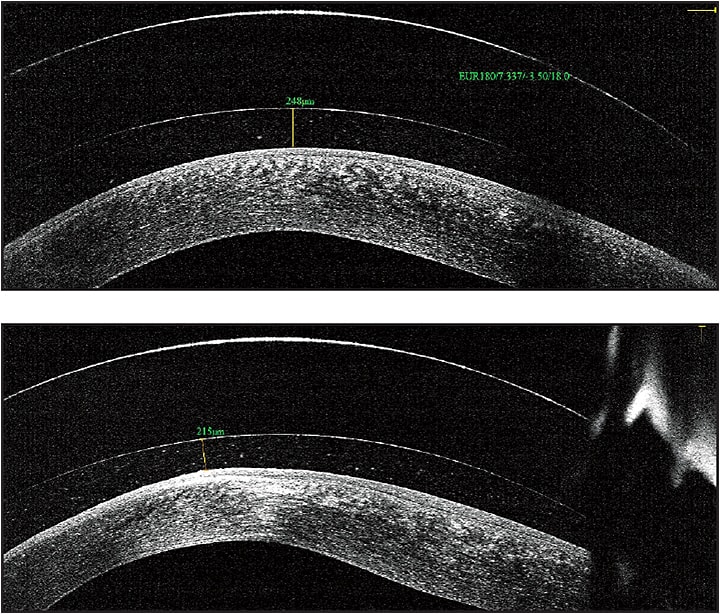

Figure 1. OCT image of a scleral lens fit on a patient who has keratoconus, horizontal line scan (top) and vertical line scan (bottom). The cornea is the opaque white band located at the bottom of each picture, the tear film reservoir is the middle clear band, and the contact lens is the top band. Using an electronic caliper tool, the precise amount of vault can be measured, leaving no doubt as to the precision of the fit.

Anterior segment OCT (AS-OCT) allows practitioners to view a cross-sectional image of a contact lens on the eye in real time and to monitor the health of the cornea in the presence of the contact lens. This view is valuable for judging the vault of new contact lens designs over the cornea and for judging where the lenses land on the eye. It is the most specific way to determine whether the lens fit is acceptable and to troubleshoot when the lenses are not fitting appropriately.